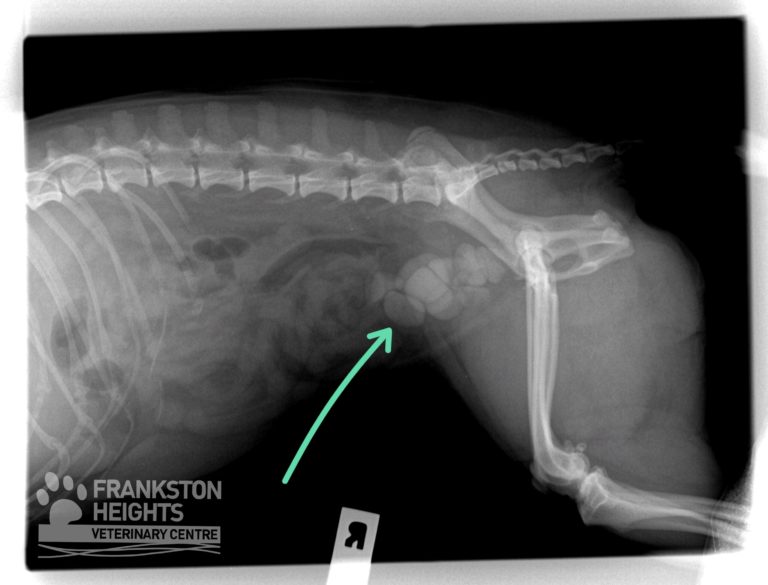

From frankstonvet.com.au

The canine bladder, cystitis & bladder stones frankstonvet vetlife Raw Food Dog Kidney Stones Raw diets offer biologically appropriate, minimally processed ingredients for optimal canine. Web with our superior, consistent fresh, natural diet using raw protein dogs can fight against diseases brought by age and. Web when dealing with dogs/cats that have kidney/bladder stones feeding a low purine raw diet is essential. Web many things can cause kidney disease in dogs, including birth defects,. Raw Food Dog Kidney Stones.